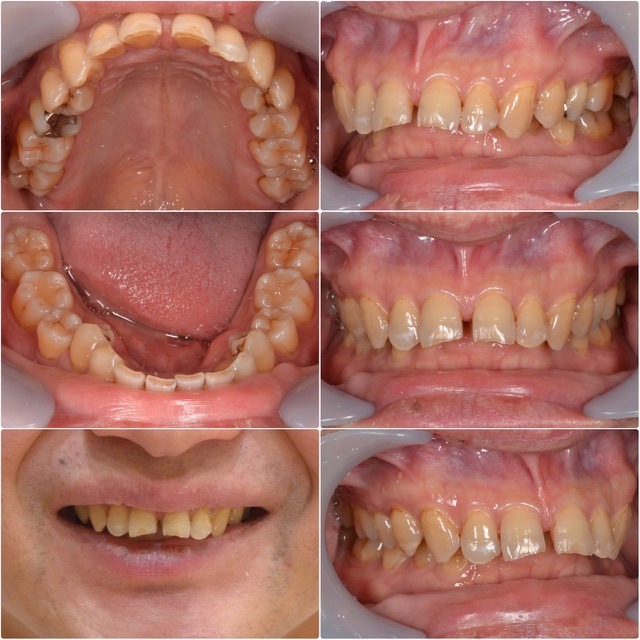

主訴・術前

メタルフリー、矯正をしたい。

主訴メタルフリー、矯正をしたい。

診断名叢生

年齢40代男性

治療方法矯正治療セラミック治療ホワイトニング

抜歯部位非抜歯

治療期間1年1ヵ月

治療費矯正治療125万円セラミック20万円/1本ホワイトニング6万円  (全て税別)